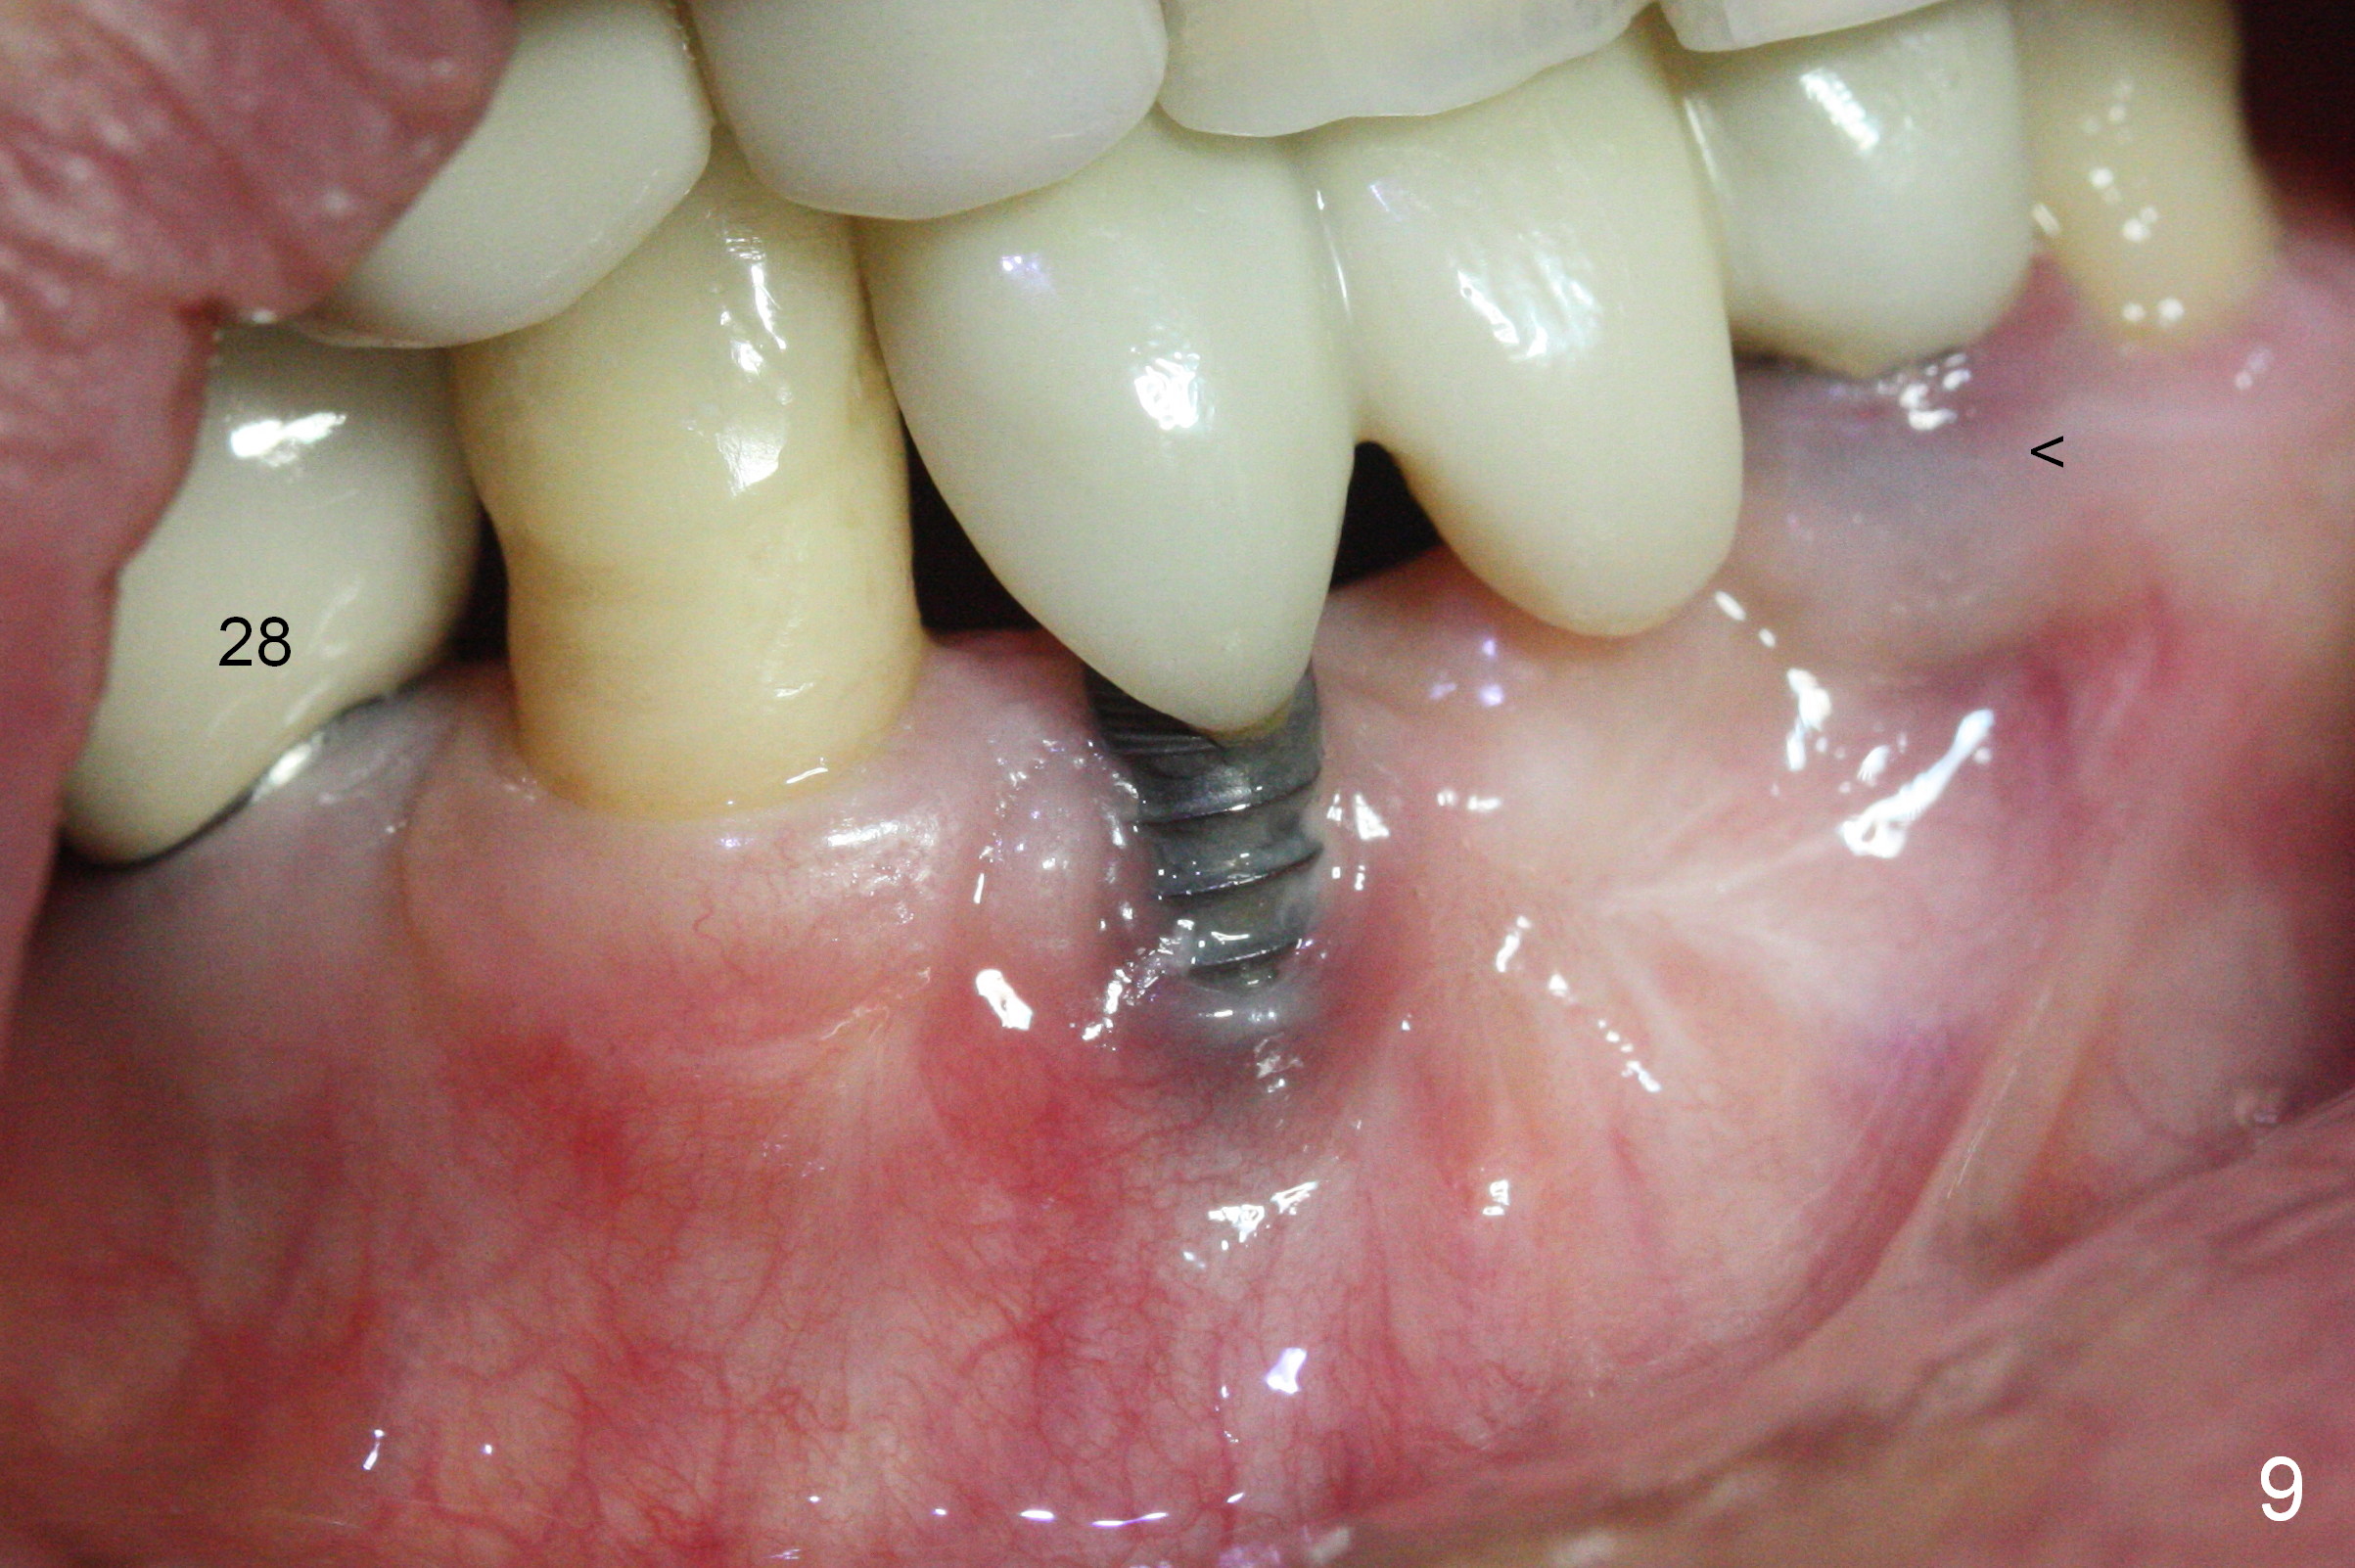

Fig.5 is taken following local anesthesia to show the exposed mesh, 22 days post placement. When the latter is removed, the exposed threads appear to be less (Fig.6, as compared to Fig.2). There is healthy granulation tissue growth apically (*). The patient is asymptomatic 1 month post mesh removal; there is no tenderness around exposed threads (Fig.7). Connective tissue graft is planned to cover the exposed threads through tunnel technique. Thread exposure appears less 3 months post mesh removal (Fig.8). There is infection when the region is not kept clean (Fig.9 (2.5 years post mesh removal)). The other 1-piece implant should have minor implant exposure (<). It appears that there is no thread exposure associated with the immediate implant at #28. Using smaller 1-piece implants (2.5 or 2.0 vs. 3 mm) with flap surgery should be able to prevent the complication. The 72-year-old phobic patient declines any further treatment. Two years later, she agrees to have treatment because of repeated infection (Fig.10). Impression has been taken for stent. After sectioning FPD and removing the infected implant (Tatum), a smaller implant will be placed in between the implants. If her vein is not too small, blood will be drawn for PRF.